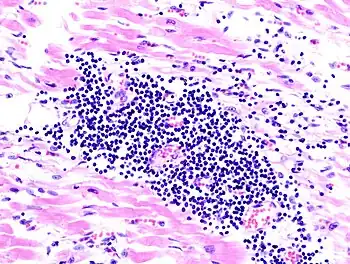

The practice of surgical pathology allows for definitive diagnosis of disease (or lack thereof) in any case where tissue is surgically removed from a patient. This is usually performed by a combination of gross (i.e., macroscopic) and histologic (i.e., microscopic) examination of the tissue, and may involve evaluations of molecular properties of the tissue by immunohistochemistry or other laboratory tests.

A biopsy is a small piece of tissue removed primarily for the purposes of surgical pathology analysis, most often in order to render a definitive diagnosis. Types of biopsies include core biopsies, which are obtained through the use of large-bore needles, sometimes under the guidance of radiological techniques such as ultrasound, CT scan, or magnetic resonance imaging. Core biopsies, which preserve tissue architecture, should not be confused with fine-needle aspiration specimens, which are analyzed using cytopathology techniques. Incisional biopsies are obtained through diagnostic surgical procedures that remove part of a suspicious lesion, whereas excisional biopsies remove the entire lesion and are similar to therapeutic surgical resections. Excisional biopsies of skin lesions and gastrointestinal polyps are very common. The pathologist's interpretation of a biopsy is critical to establishing the diagnosis of a benign or malignant tumor, and can differentiate between different types and grades of cancer, as well as determining the activity of specific molecular pathways in the tumor. This information is important for estimating the patient's prognosis and for choosing the best treatment to administer. Biopsies are also used to diagnose diseases other than cancer, including inflammatory, infectious, or idiopathic diseases of the skin and gastrointestinal tract, to name only a few.